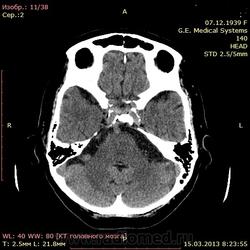

А как по мне, то тут геморрагический инсульт. Есть дислокация срединных структур слева.

Геморрагический инфаркт левой височной доли (в проекции таламуса слева) как правильно по локализации сам не знаю, скорее все таки таламус, со смещением срединных структур вправо, третий и левый боковой желудочек частично компримированы, формируется зона перифокального отека

тут либо геморрагический инсульт с перифокальным отеком, либо ишемический инсульт с геморагическим пропитыванием. Как их различить? Что скажут опытные коллеги?

Типичное медиальное кровоизлияние (в таламусе, медиальнее внутренней капсулы), уже не совсем свежее, плотность уже более низкая и зона отека приличная.

КТ признаки кровоизлияния в базальных ядрах, отделах с выраженными признаками перифирического отека. Про давность - сами пусть спросят , но скорее не свежак, до 5-6 дней.

Описывайте как геморрагический инсульт с объемным действием (смещением) на срединные структуры мозга. Померяйте плотности для оценки стадии. А различить на КТ две обговариваемые формы думаю нельзя. Разве что при пропитывании не будет такой четкой динамики изменения плотности очага. В литературе не встречал.